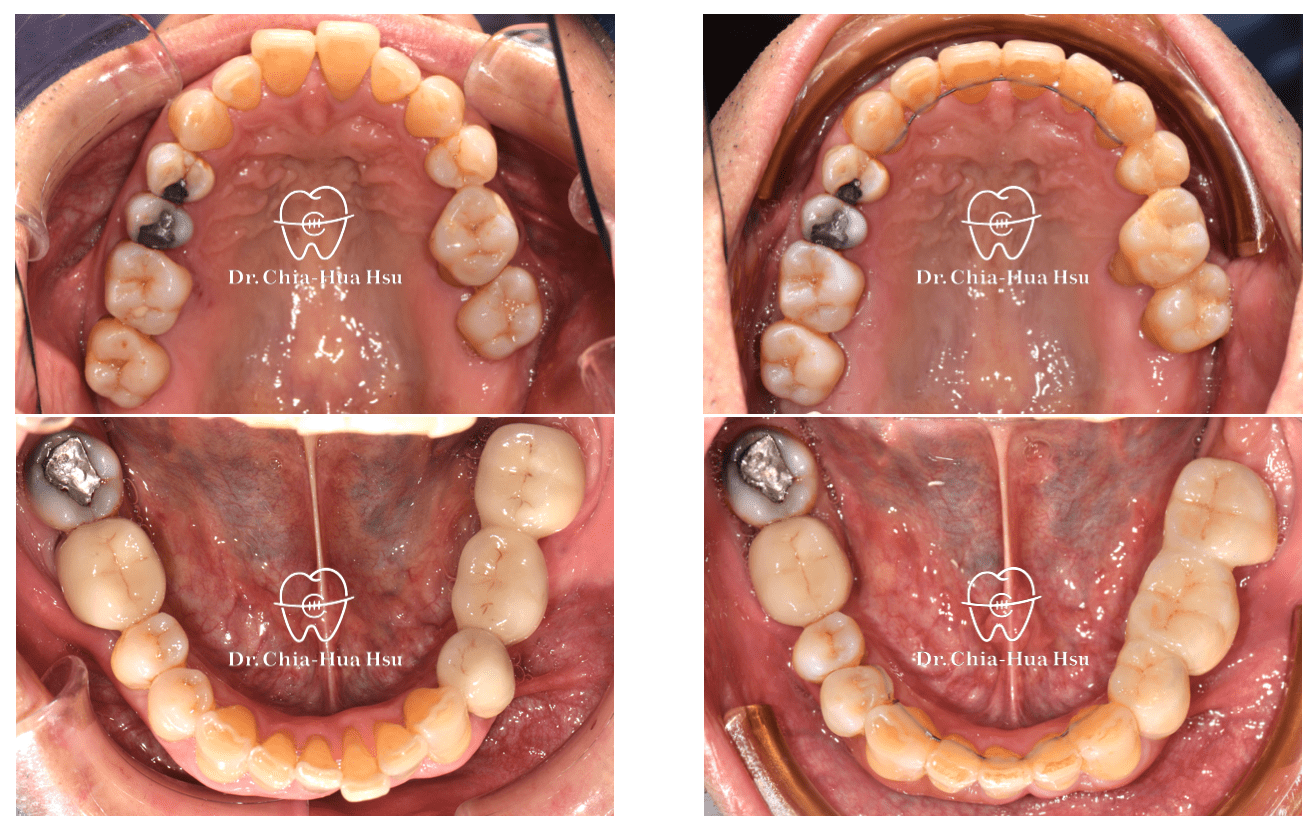

• 這位六十幾歲退休的先生,年輕時有做過矯正治療,年紀大了以後因為牙周病的關係牙齒又亂掉,因此來找許醫師做二次矯正治療。

• 問題分析:患者除了暴牙、牙齒不整齊和黑三角縫明顯,還有牙周病的問題。

• 治療方式:在病患牙周治療結束後,與患者討論治療方案,最後使用對牙周健康友善的隱適美治療,並搭配上顎骨釘的使用,來改善患者的暴牙與齒列不正。後續也透過美學樹脂補牙來處理患者下顎門牙黑三角縫的問題。

治療前

治療後